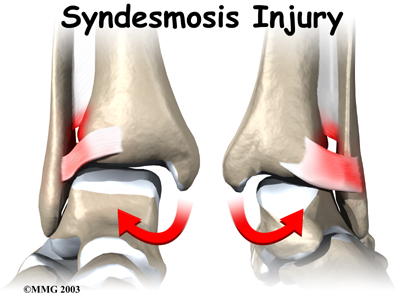

Doctors do not completely understand how syndesmosis injuries occur, though they appear to happen most often when the foot is forced upward and outward. Such injuries frequently happen in high-level football players, although snow skiers also account for a high percentage of syndesmosis injuries.

An ankle syndesmosis injury involves a sprain of one or more of the ligaments that support the ankle syndesmosis. A ligament is made up of multiple strands of connective tissue, similar to a nylon rope. A sprain stretches or tears the ligaments. Minor sprains only stretch the ligament. A tear may be either a complete tear of all the strands of the ligament or a partial tear of only some of the strands. The ligament is weakened by the injury. How much it is weakened depends on the degree of the sprain.

Mild syndesmosis sprains usually involve a stretch or slight tear in only one of the ligaments making up the syndesmosis. Moderate tears of the ankle syndesmosis may lead to ankle joint instability, which make the ankle mortise loose. In severe tears of the ligaments, the ends of the tibia and fibula actually spread apart. This condition is called diastasis.